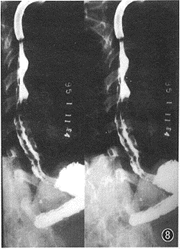

4.远段食管蠕动微弱,钡团停滞:主要见于累及平滑肌的疾病,如结缔组织病,以皮肌炎和硬皮病的表现最为明显和典型(图8,9)。

图8 皮肌炎病人,气管插管后作EDR,2次点片示食管各段均无蠕动,LES开放;食管下段黏膜皱襞粗大为返流性食管炎表现

, http://www.100md.com

图9食管下段无蠕动,呈枯枝状,为返流性食管炎的少见表现